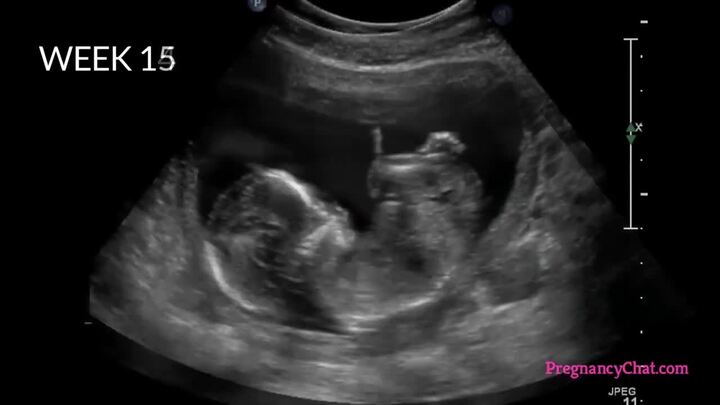

Tiến trình thai nhi lớn lên từ khi trứng gặp tinh trùng

Thai nhi bắt đầu cuộc sống của mình ngay từ trong bụng mẹ, vì vậy, ngay từ trước khi chào đời, bé đã có thể làm được rất nhiều việc tuyệt vời, ngoài sức tưởng tượng của mẹ.